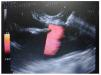

Figure 2. Injection of 1% lidocaine.

Materials and methodsIn a retrospective analysis of data obtained prospectively the records of patients with pain caused by pancreatic cancer who underwent EUS CPN at the Instituto Nacional de Ciencias Médicas y Nutrición “Salvador Zubirán” from March 2005 to May 2007 were evaluated. All patients have unresectable pancreatic cancer confirmed by computed tomography (CT), magnetic resonance imaging (MRI) and/or EUS; EUS criteria and fine-needle aspiration (FNA) were used when a tissue diagnosis was not available before EUS. They underwent to EUS CPN during the same EUS procedure for diagnosis. Before the procedure all patients had laboratory tests including prothrombin time and full blood count. The patients were placed in left decubitus position and sedated by using a combination of midazolam, propofol and phentanyl by anesthetist. Patients were continually monitored with an automated noninvasive blood pressure device, electrocardiogram, and pulse oximetry throughout the procedure. EUS CPN was performed with a linear array echoendoscope GFUCT-140 (Olympus) by an experienced echoendoscopist. The angle formed by the aorta and celiac trunk was identi- fied through the posterior gastric wall. Under direct EUS visualization, a 22 gauge, 8 cm aspiration needle (Wilson-Cook Medical, Inc. Winston-Salem, N.C.) primed with normal saline solution was placed immediately adjacent and anterior to the aorta at the level of the celiac trunk (figure 1). After injecting 2 mL of saline solution to clear the needle, an aspiration test was performed, if no blood was obtained, 10 mL of 1% lidocaine was injected (figure 2). The aspiration test was repeated, and if no blood, 20 mL of dehydrated 98% absolute alcohol was injected. The needle was then flushed with 3 mL of saline solution and withdrawn from the patient. After the procedure a Doppler ultrasound of the celiac trunk and aorta was made to evaluate permeability. The average estimated time for the EUS CPN portion of the procedure was 10 minutes. After the procedure all patients remained under observation for at least 2 hours to rule out any complications. All patients were reevaluated for complications 7 days after the procedure. Dosage and class of pharmacologic treatment were evaluated before the procedure as well as 15 days and 30 days after procedure. Measurement of intensity of pain was made with a validated visual analog pain scale (0-10) in all patients6 by a pain specialist. Measurements two and four weeks after the procedure were made. The complications related to the EUS CPN were determined in agreement with the medical records. Medians, ranges and proportions were used to summarize the demographics and clinical variables. EUS CPN pain scores paired before and after (15 and 30 days) were compared with the Friedman test.